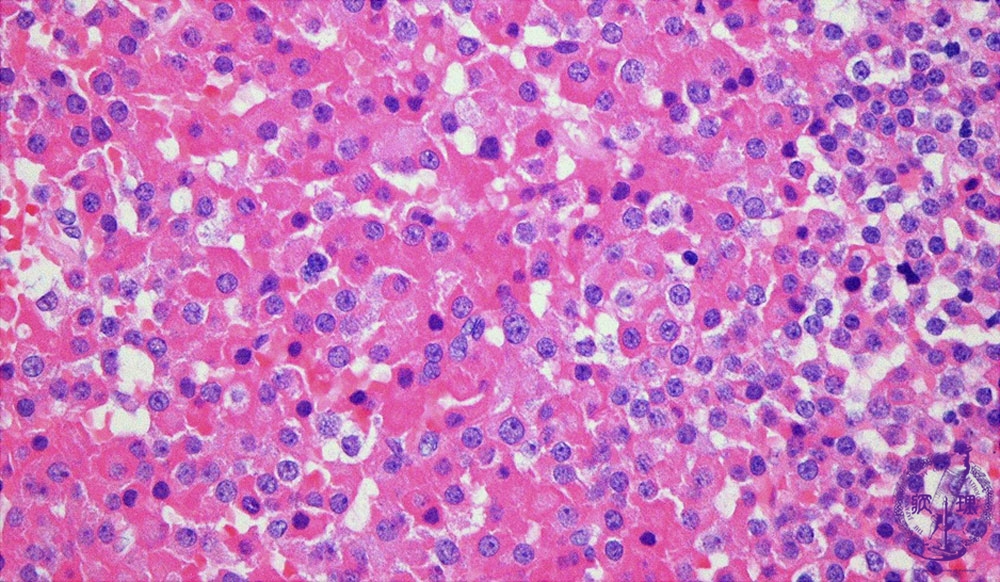

Microscopic findings (HE stain, high power view). Growth hormone producing pituitary adenoma. Tumor cells with eosinophilic cytoplasm are arranged in sheet-like architecture.